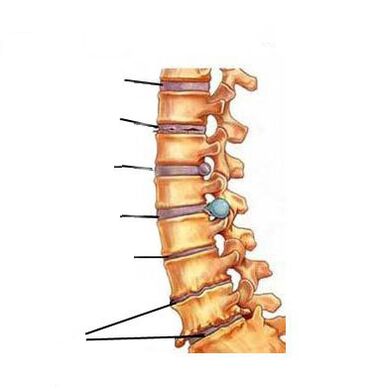

Ang antas ng pag -unlad ng sakit

Ang cervical osteochondrosis, tulad ng osteochondrosis ng iba pang mga gulugod, ay bubuo sa mga yugto. Mayroong 3 yugto ng pag -unlad ng sakit.

1 degree

Ito ay nailalarawan sa simula ng pagkawasak ng mga intervertebral disc.

Ang mga bitak ay bumubuo sa fibrous singsing, ang lakas at pagkalastiko ng disk ay nabuo, bumababa ang taas nito, dahil sa kung saan ang mga ugat ng nerbiyos ay pinisil.

Lilitaw ang isang katangian ng sakit na sakit. Minsan sa 1 yugto (preclinical) ang nasabing sakit ay maaaring wala, at ang osteochondrosis ay nagpapatuloy na may katamtamang kakulangan sa ginhawa sa leeg.

2 degree

Kung ang osteochondrosis ng 1st degree ay hindi ginagamot o ang paggamot ay hindi epektibo, kung gayon ang isang talamak na kondisyon ay nangyayari, na kung saan ay ang ika -2 antas ng osteochondrosis.

Ang sakit ay nagiging pare -pareho, ang pagkawasak at selyo ng intervertebral disc ay nagpapatuloy at humahantong sa maliit na dislocations ng cervical vertebrae.

Sa cervical osteochondrosis, ang isang bumabagsak na sindrom ng ulo ay maaaring umunlad sa yugtong ito. Ang sindrom na ito ay nailalarawan sa pamamagitan ng matinding sakit, at ang isang tao ay pinipilit na suportahan ang kanyang ulo sa isang nakapirming estado upang mabawasan ang sakit.

3 degree

Ang cervical osteochondrosis ng ika -3 degree ay sinamahan ng mga sumusunod na palatandaan:

- sakit ng ulo;

- pagduduwal;

- pagkahilo;

- cervical "bastards";

- Paglabag sa pagiging sensitibo ng itaas na mga paa't kamay.

Ang fibrous singsing ay halos nawasak, na humahantong sa mga komplikasyon ng osteochondrosis - protrusion ng intervertebral disc o intervertebral hernia.

Sa 3 yugto ng osteochondrosis, ang intensity ng sakit ay maaaring bumaba, dahil ang apektadong cartilaginous tissue sa intervertebral disk ay hindi umiiral, na nangangahulugang walang mapagkukunan ng sakit, ngunit ang pinching ng mga ugat ng nerbiyos ay nananatili, kaya ang sakit ay hindi ganap na umalis.